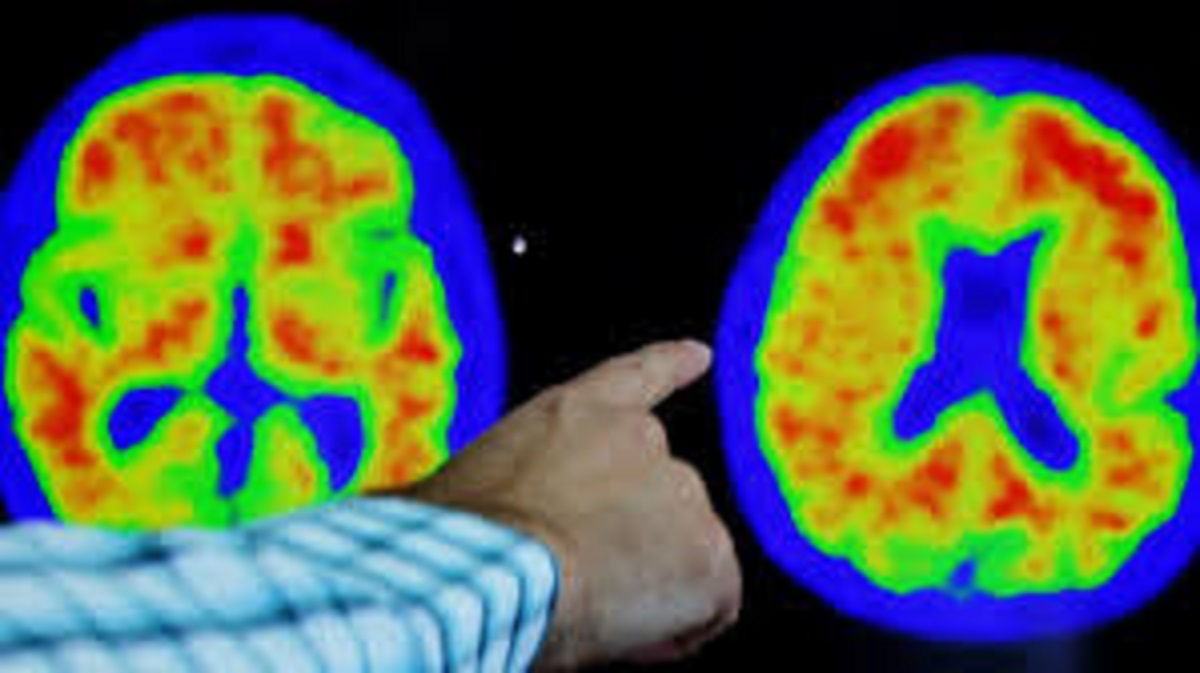

SA warned of sharp rise in dementia cases by 2050

Health experts are warning that South Africa (SA) could see a dramatic increase in dementia cases